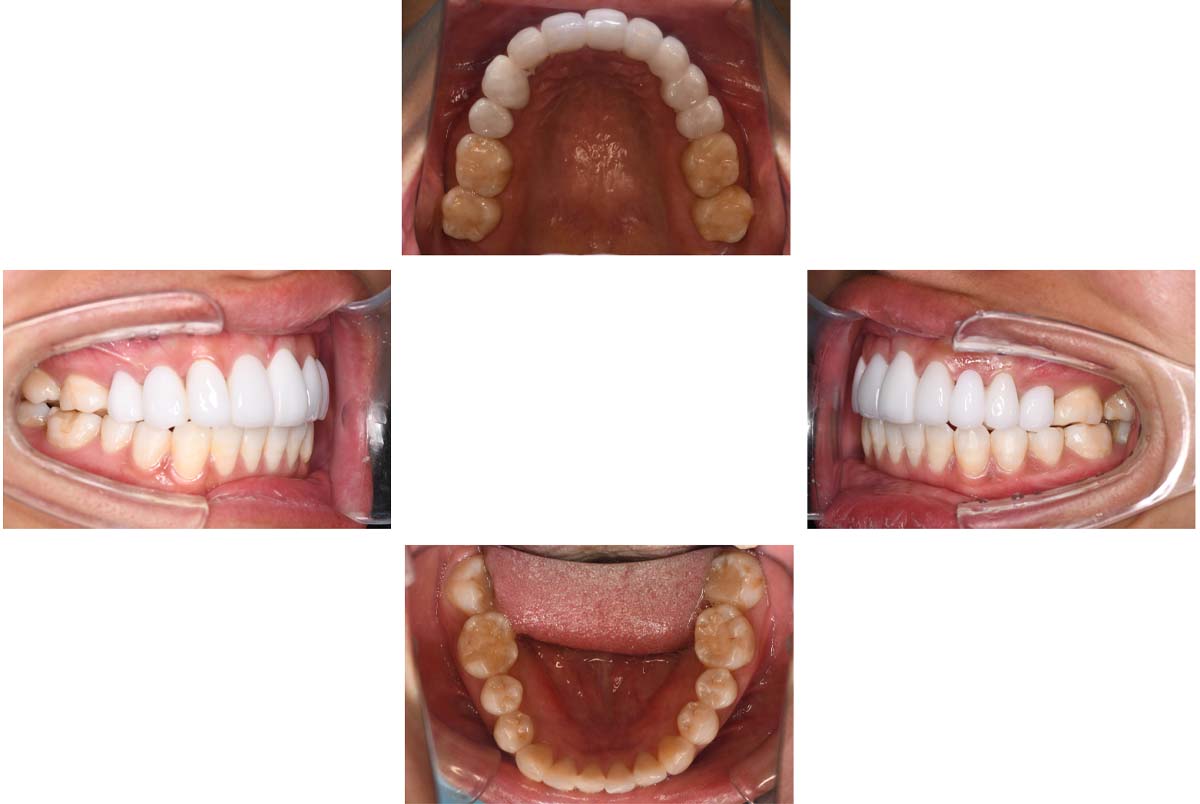

副子なし 副子あり

バイトアップ後